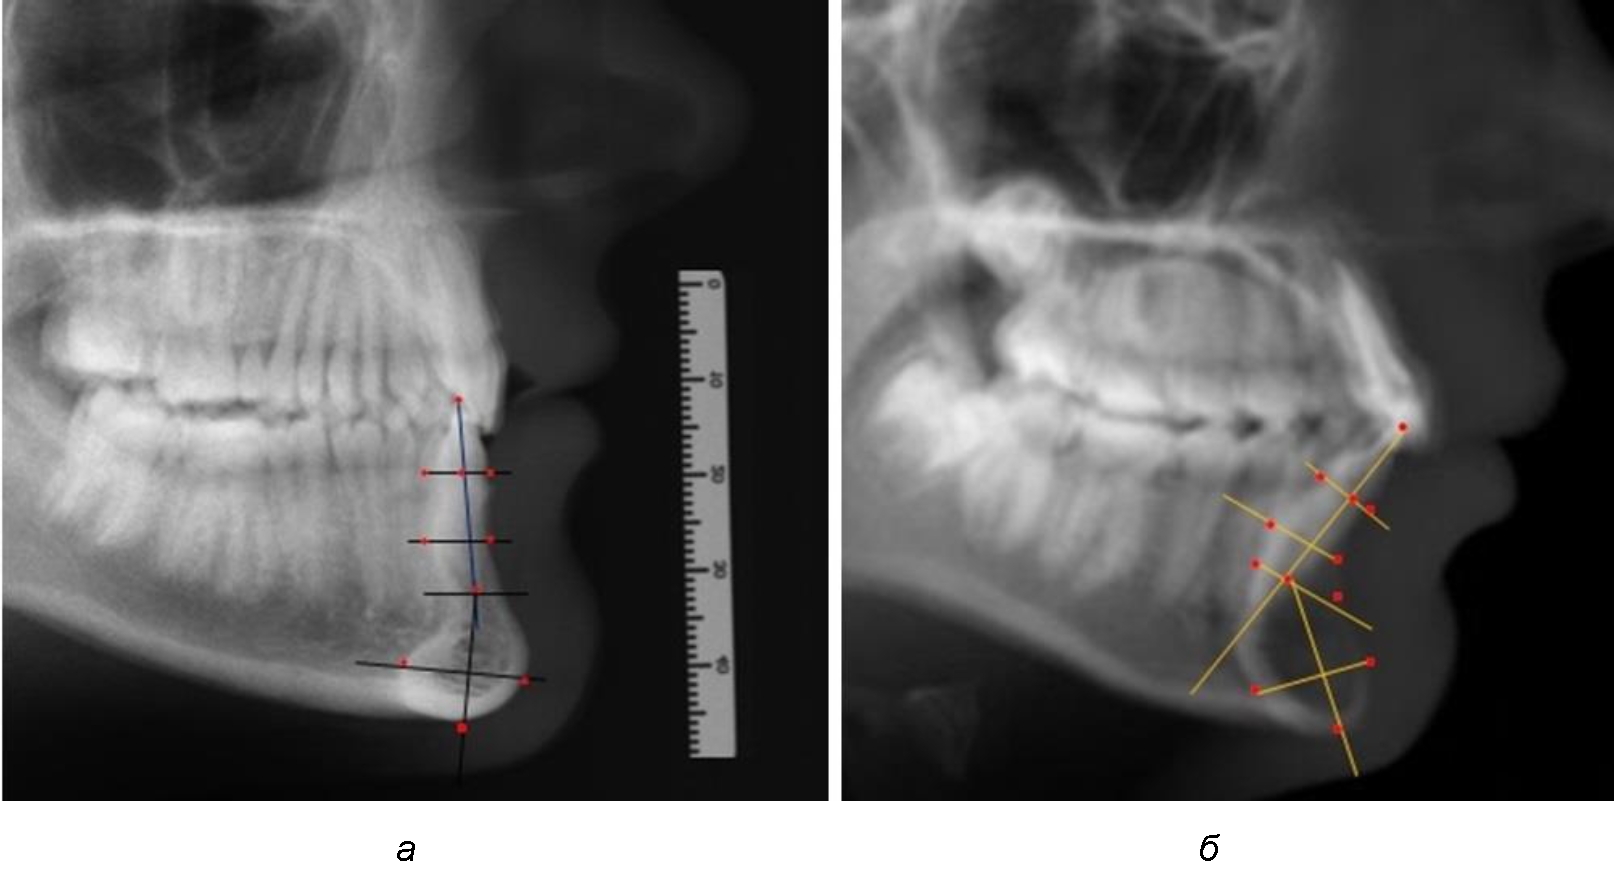

При необходимости и/или возможности проведения КЛКТ-исследования проводили анализ с сопоставлением фрагмента, что повышало точность диагностических мероприятий (рис. 2).

Рис. 2. Фрагменты ТРГ с ориентирами для измерения параметров резцового сегмента (а) и с наложением фрагмента КЛКТ (б)

Нередко отмечается деформация подбородочного выступа и различное его положение по отношению к зубоальвеолярной части сегмента. При мезиальной окклюзии нередко нижняя подбородочная точка смещается кзади по отношению к условной срединной вертикали нижнего резца, а при дистальной окклюзии отмечается компенсаторное отклонение подбородка кпереди (рис. 5).

Рис. 5. Особенности нижнечелюстного резцового сегмента на ТРГ у людей при мезиальной (а) и дистальной (б) окклюзии

Кроме того, так же как и у людей с физиологической окклюзией, определялось различие в положении апикальных точек Downs и Schwarz, что, по нашему мнению, может определять тактику лечения патологических форм протрузии/ретрузии резцов с учетом биотипа костной ткани.